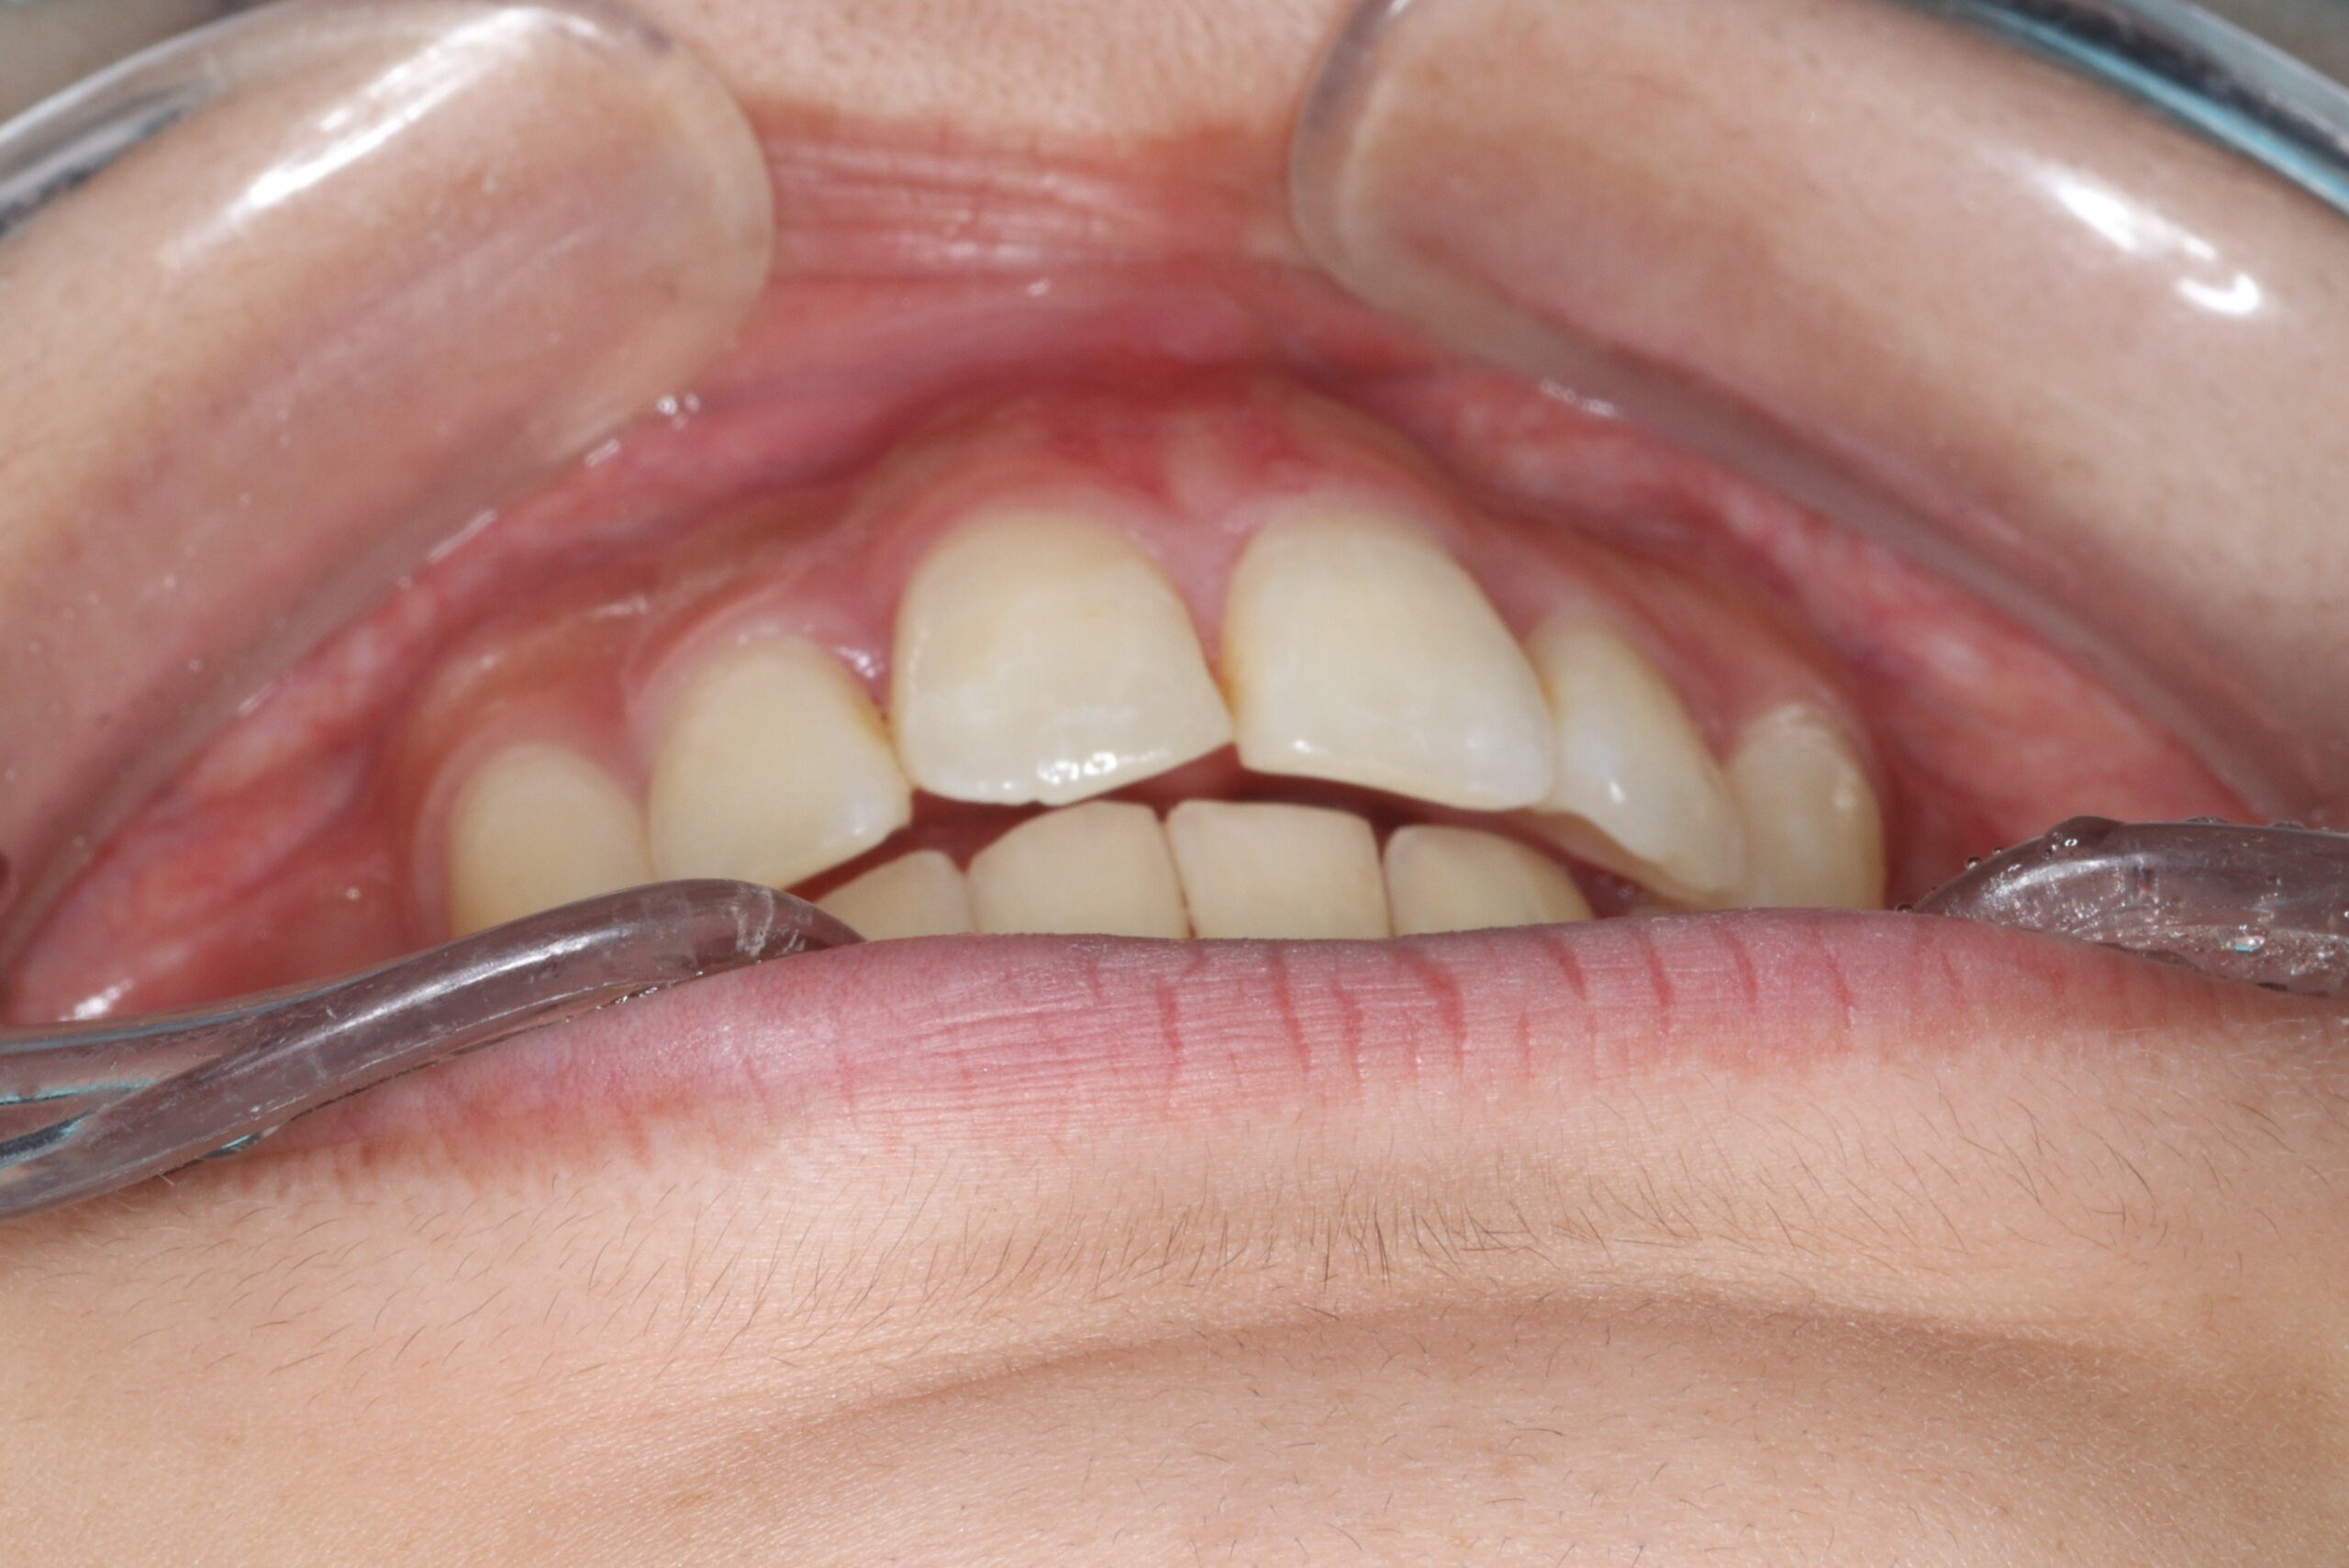

矯正術後:前歯部あおり

矯正術前:オーバージェット

矯正術後:オーバージェット